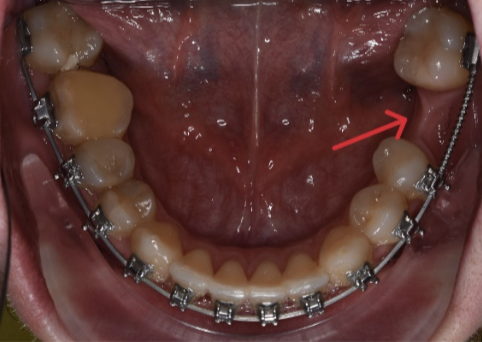

Aici avem un caz in care inghesuirea dentare grava s-a rezolvat prin tratament orthodontic cu extractii dentare.

Se poate observa ca nu exista spatiu pentru eruptia caninilor.

S-a realizat extractia a 2 premolari:

Iar acesta este aspectul final: